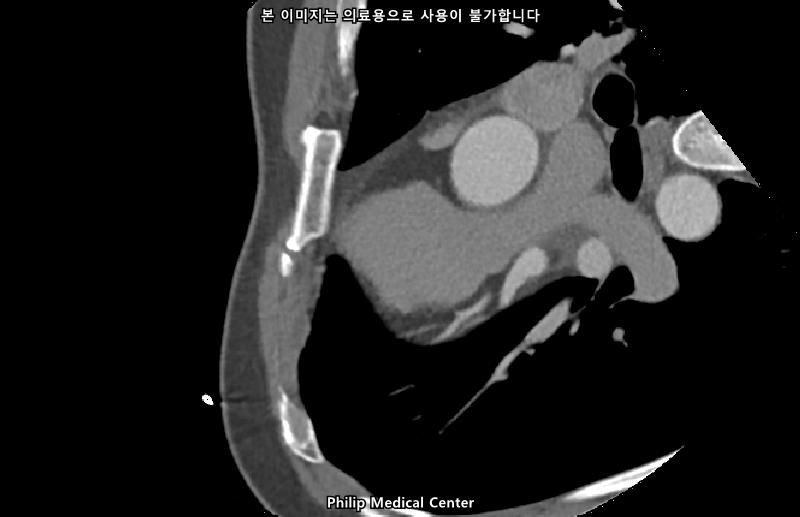

• 4번 째 사진

• 올리신 사진들을 통해서는 폐를 평가할 수 없습니다.

우측 폐첨부에 경미한 섬유성변화와 우중엽에 약 3mm크기의 결절이라는 것은 이상 소견이긴 하지만 보통 경과관찰을 하는 소견입니다.